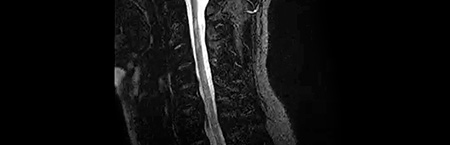

• Ressonância magnética do neuroeixo

Ressonância magnética

• Carga lesional extensa

• Inúmeras novas lesões em relação a RM prévia